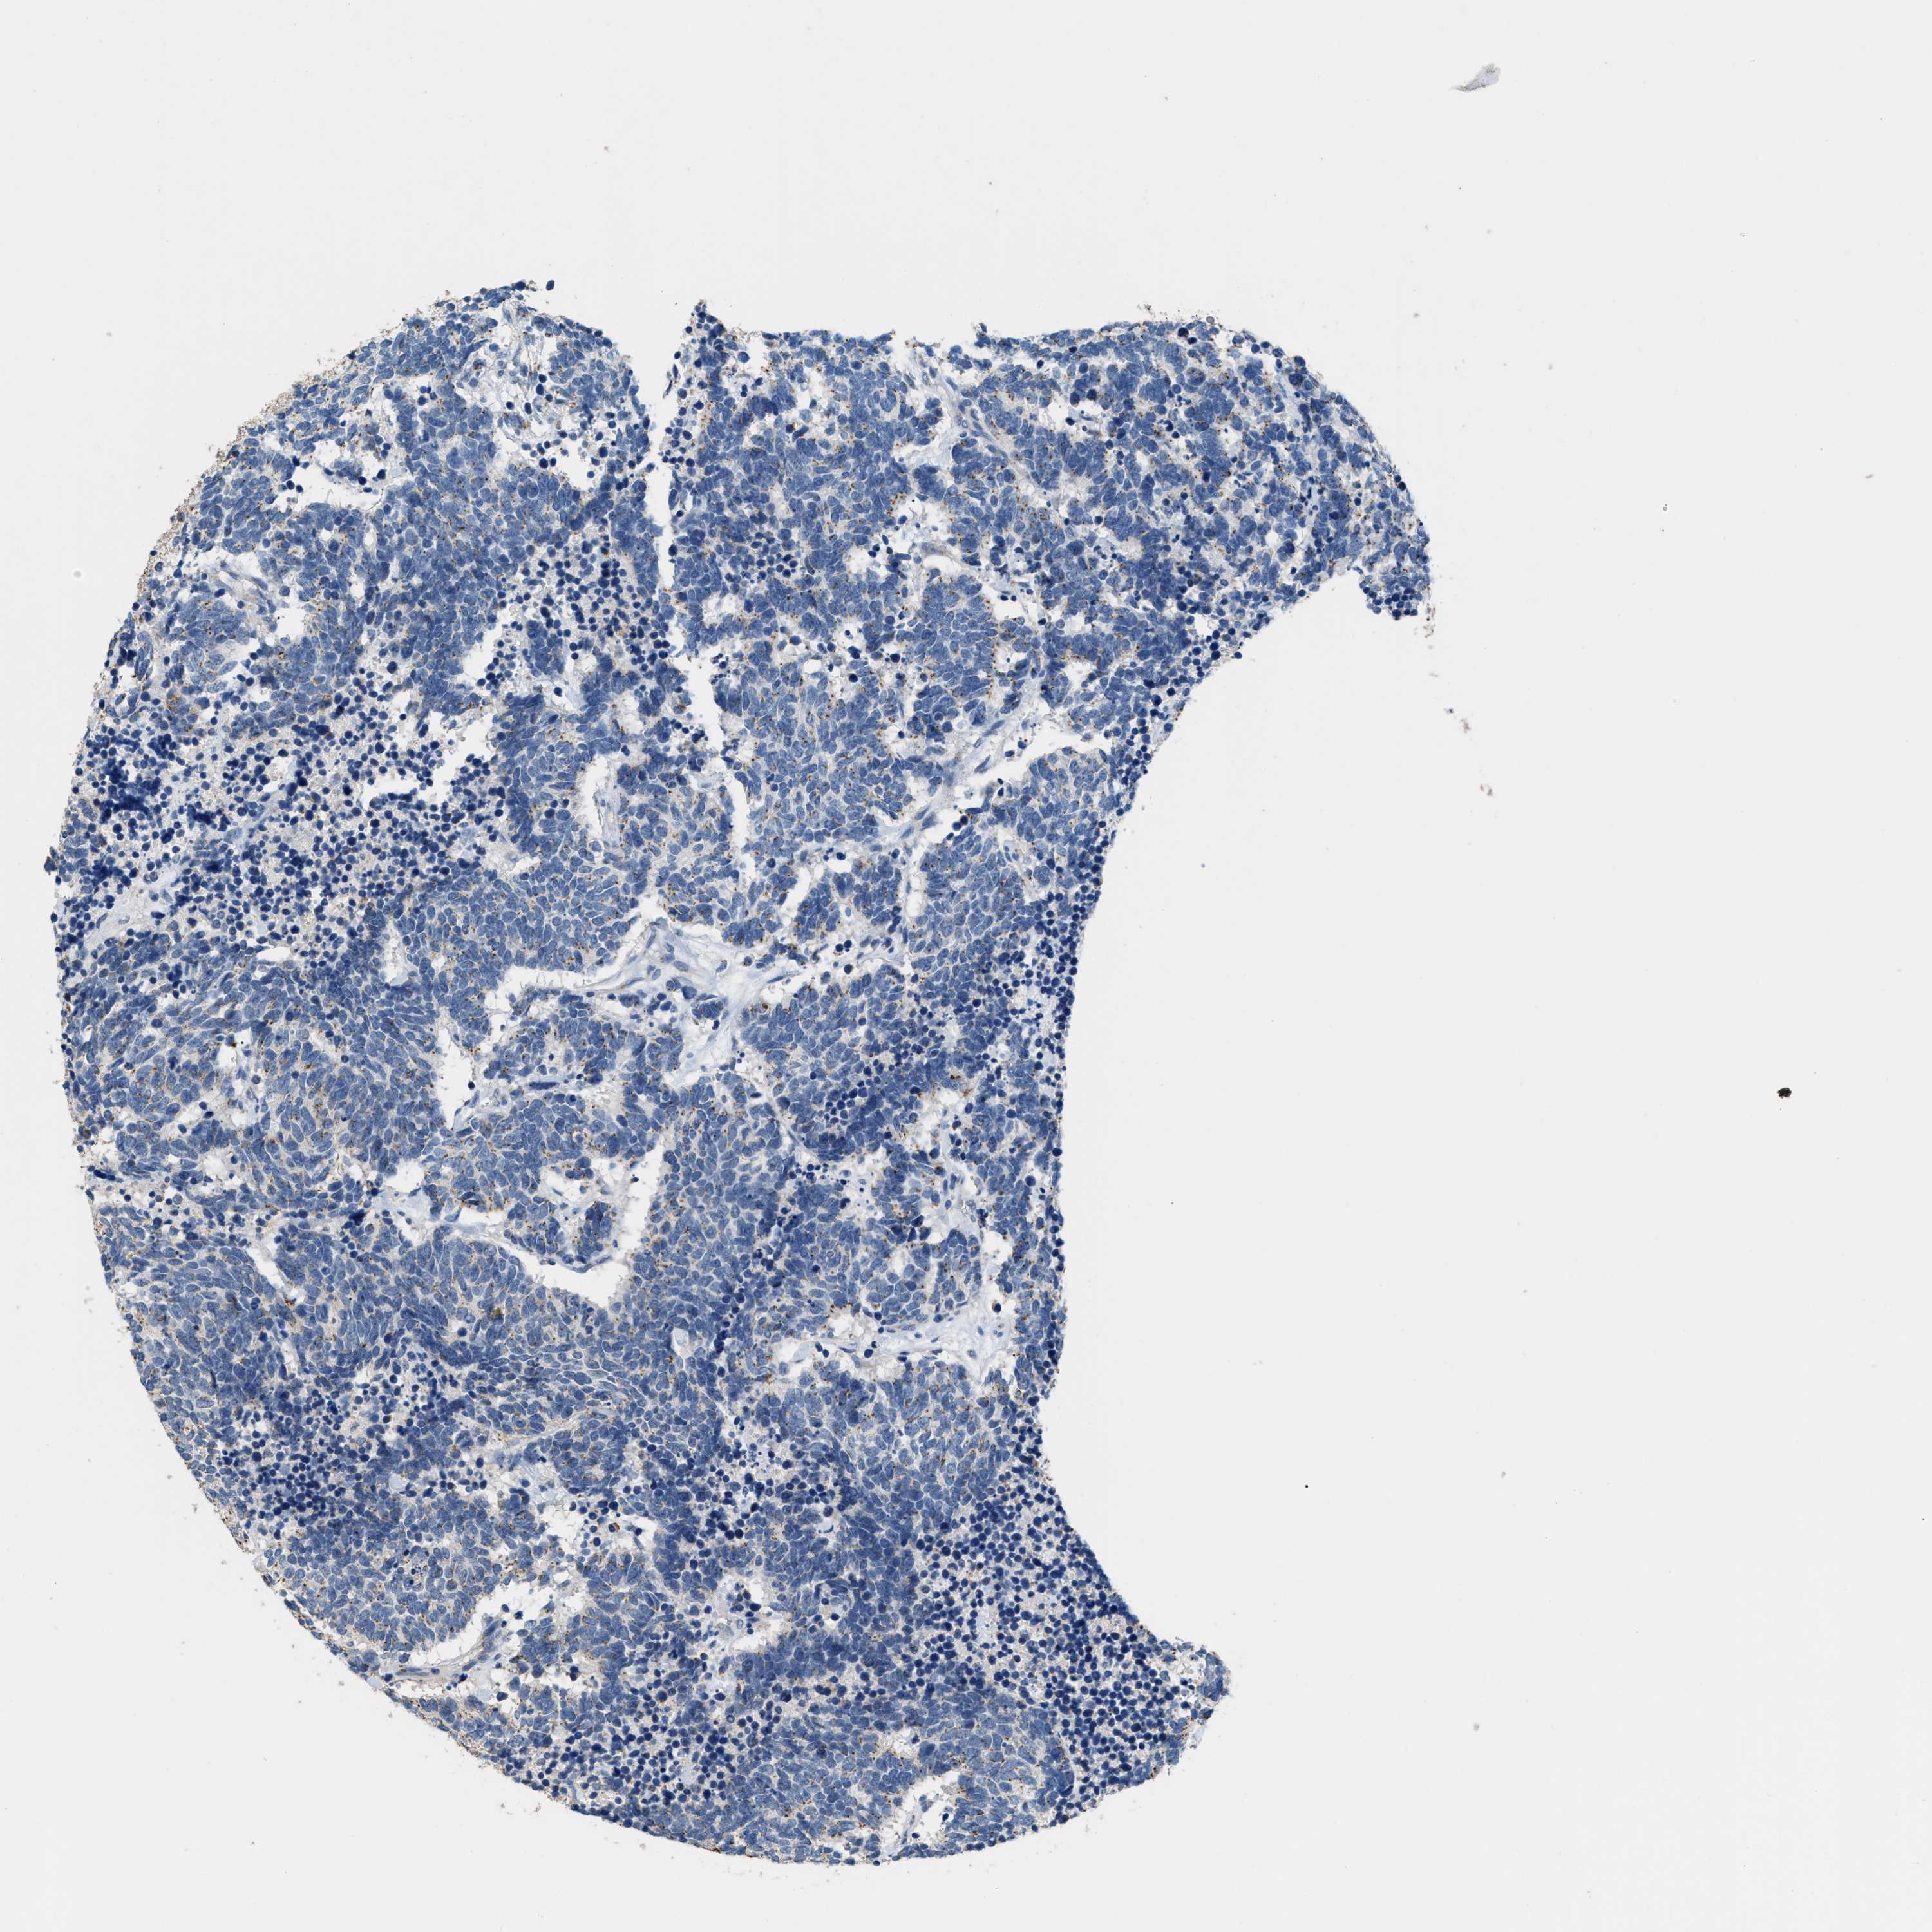

CARCINOID - Protein expressioni

A mouse-over function shows sample information and annotation data. Click on an image to view it in a full screen mode. Samples can be filtered based on level of antibody staining by selecting one or several of the following categories: high, medium, low and not detected. The assay and annotation is described here.

Antibody stainingi

Antibody staining in the annotated cell types in the current human tissue is reported as not detected, low, medium, or high, based on conventional immunohistochemistry profiling in selected tissues. This score is based on the combination of the staining intensity and fraction of stained cells.

Each image is clickable and will lead to virtual microscopy that enables deeper exploration of all samples and also displays staining intensity scores, fraction scores and subcellular localization as well as patient and tissue information for each sample.

Antibody HPA010638

Staining

Not detected

Negative

None

Carcinoid, malignant, NOS